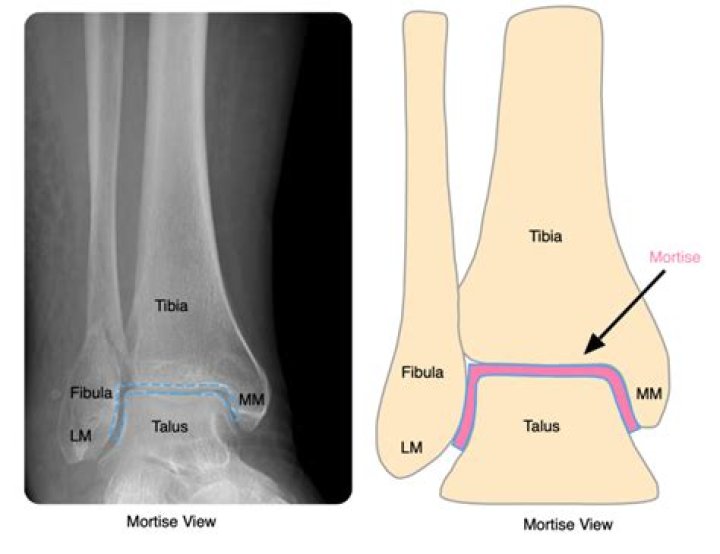

What joints make up the ankle mortise

The ankle joint is a hinged synovial joint that is formed by the articulation of the talus, tibia, and fibula bones. Together, the three borders (listed